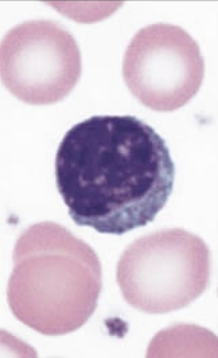

How to identify lymphocytes?

Large nucleus, thin cytoplasm